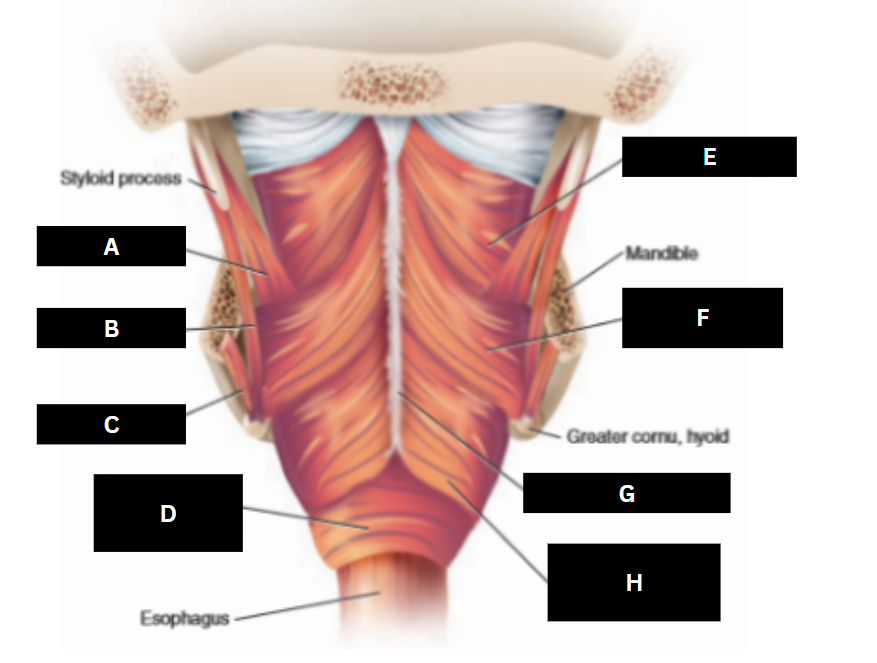

Stylopharyngeus

A

Styloglossus

B

Stylohyoid

C

Cricopharyngeus

D

Superior pharyngeal constrictor

E

Middle pharyngeal constrictor

F

Pharyngeal raphe

G

Inferior pharyngeal constrictor

H